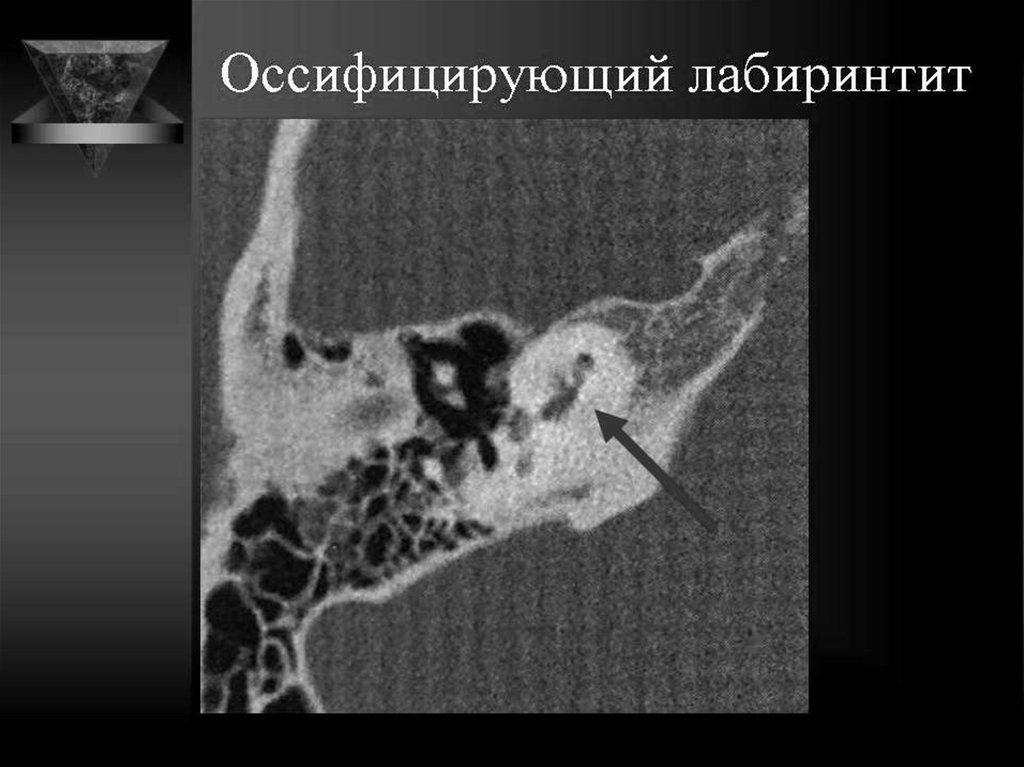

168. Оссификация лабиринта

• Оссификация лабиринта – процесс формирования

новой костной ткани в просвете костного

лабиринта, ведущее к нарушению слуховой и

вестибулярной функции.

• Оссификация лабиринта нередко сопровождает

сенсоневральную тугоухость высокой степени и

глухоту, в особенности у лиц, перенесших

менингит, травмы височной кости, различные